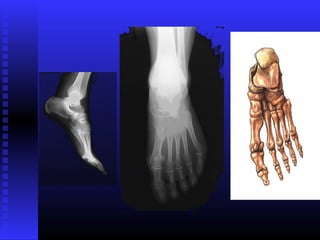

 LONGOSLONGOS

LONGOSLONGOS